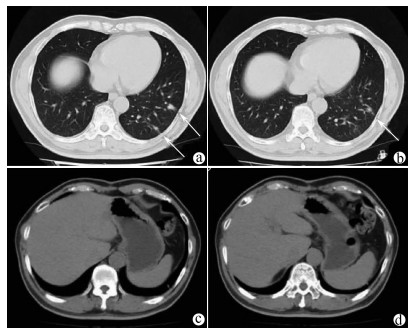

Complete remission after comprehensive treatment of lung metastases following liver cancer surgery: A case report